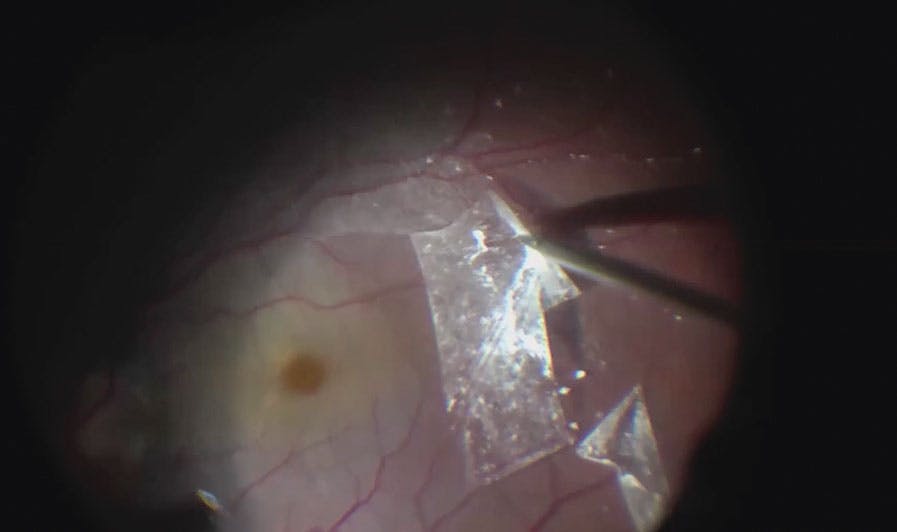

Ten years after the initial presentation, the patient was scheduled for a second surgery due to VA worsening to 20/63 OD and recurrence of macular detachment. During reoperation, we removed a portion of the residual posterior hyaloid and used a free ILM piece to fill the pit; the remaining ILM flap was inverted over the pit. After fluid-air exchange, we filled the eye with 15% SF6. One month later, there was no SRF on spectral-domain OCT (SD-OCT), and VA improved to 20/40 OD over 15 months.

The second case involved a 15-year-old boy with optic disc pit maculopathy in his left eye. Preoperative VA was 20/63 OS. The patient underwent 23-gauge PPV with PVD. We peeled the ILM, used a free ILM flap to plug the optic pit, and filled the eye with 15% SF6. Four months after surgery, there was complete macular reattachment. VA improved to 20/25 OS and was stable until last follow-up 4 years after the intervention.

The third case involved a 13-year-old girl with optic disc pit maculopathy and VA of 20/50 OD due to a large macular detachment. We performed PPV and PVD and used a free ILM flap to fill the pit. After fluid-air exchange, we filled the vitreous cavity with 20% SF6 (Video). Three months postoperatively, VA reached 20/25 OD and SRF progressively disappeared over 9 months (Figure). Two years later, visual acuity and macular integrity remained stable.

For each ILM plugging procedure, there were no surgical complications, but these can include mechanical damage and toxicity of different materials to the optic nerve fibers and formation of macular holes after ILM peeling.2,3,7 The latter can be avoided with fovea-sparing ILM peeling.

Several materials have been used to plug the pit, including scleral autograft, fibrin sealant, amniotic membrane, and autologous platelets. ILM is a good option because it does not cause inflammation and it is already in place. Peeling of the ILM can ensure complete hyaloid removal and eliminate traction. ILM can act as a scaffold for the proliferation of Müller cells and consequential gliosis, further contributing to the barrier.7